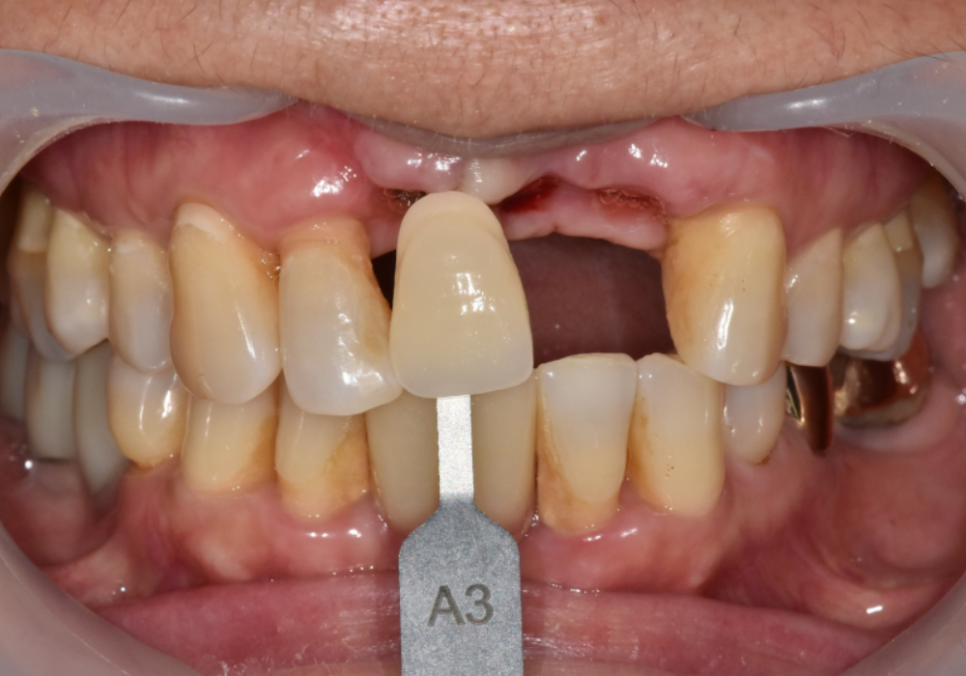

이 환자분은 “앞니가 흔들린다"는

불편감으로 오셨습니다.

확인해 보니 왼쪽 앞니는

오래전에 이미 임플란트를 해두신 상태였고,

임플란트 양옆의 치아가

흔들리는 상황이었습니다.

230826

230826(전) 240619(후)